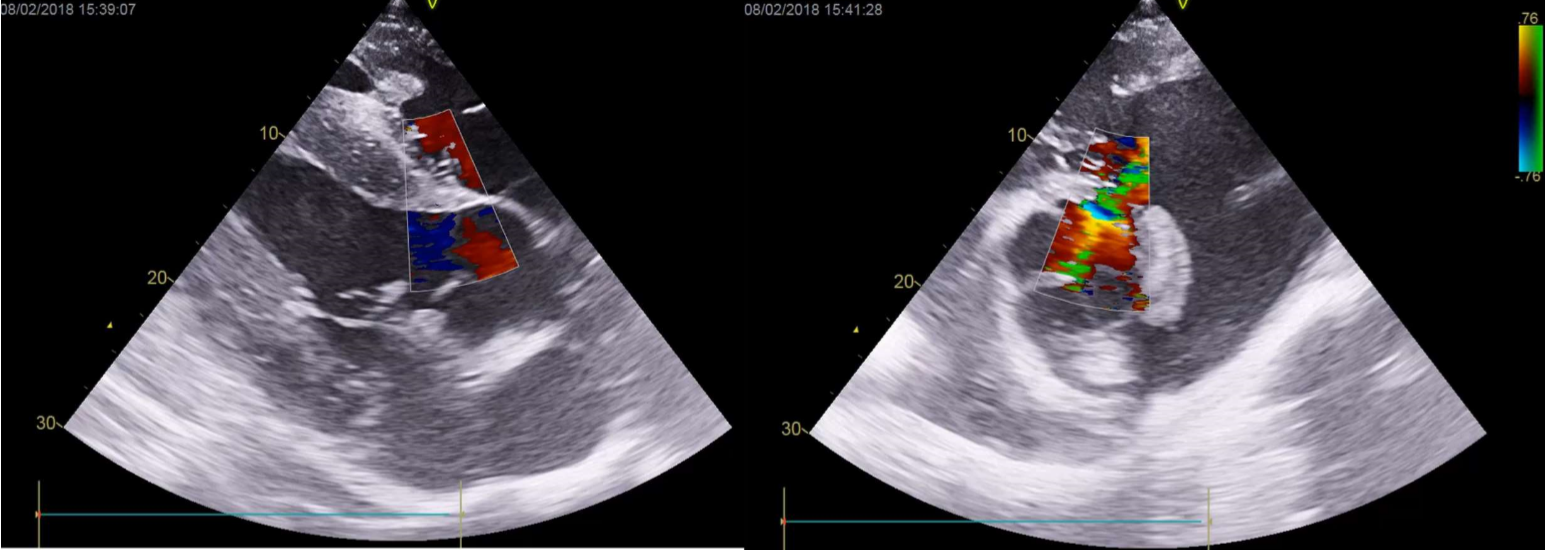

• VSD's are the most common congenital heart defect with some breed predisposition (Section A Welsh Mountain ponies, standardbreds and Arabians). It can be a standalone deflect or be a component of more complex congenital cardiac defects.

• Scarborough Flyer is a 16 year old TB and ex-racehorse. He is now a teaching horse at SVMS. He has loud bilateral systolic murmur which is loudest on the right hand side, he is otherwise bright and well. what defect is present?

VSD